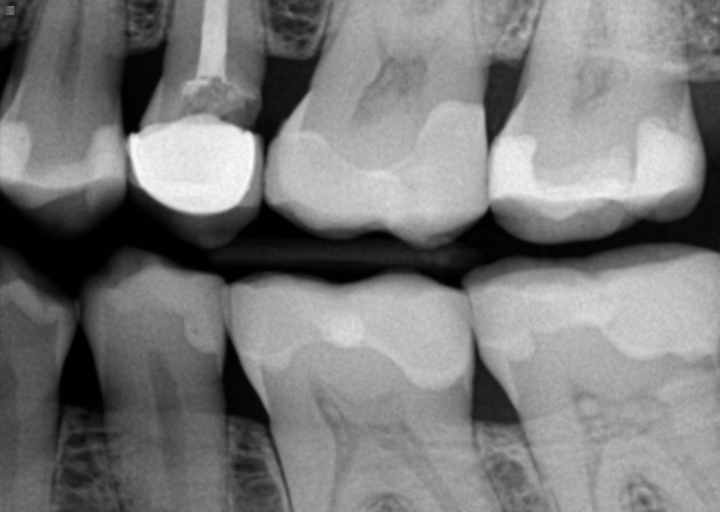

I have a good set of teeth minus my top front tooth. I broke it in half on asphalt, had a temp filling for 10 years and then got a crown. The crown left my tooth hurting so eventually ended up getting a root canal. Now almost a year later at my routine exam they did x-rays and found a fracture on the tooth. The crown is not fractured but the nub of a tooth underneath is....my dentist thinks it likely fractured during the root canal procedure. Currently I have no pain or issues, but I'm wondering what the long term worse case scenario would be or what I should be looking for as a sign of deeper ongoing damage or anything else I should be looking to do now to prevent worse damage later.

Unfortunately, there are not many options for a fractured tooth. If the tooth is fractured above the bone level, many times it can be restored with a root canal and crown. The tooth may or may not require a post and buildup depending on the amount of healthy tooth structure remaining. Once the tooth has had a root canal and a fracture occurs, the long-term prognosis becomes guarded. The tooth will be monitored periodically or until symptoms arise. Depending on the depth of the fracture it could be weeks, months, or years before treatment is needed. Ultimately, the tooth will need to be removed and replaced with a dental implant, fixed bridge, or removable partial denture. The best option, if you are a candidate, is a dental implant. Most insurance plans do not cover dental implants, therefore it is a good idea to prepare financially for the procedure if necessary. Speak with your dentist about the best option for you based on your oral health, so you can be prepared if/when the time comes.